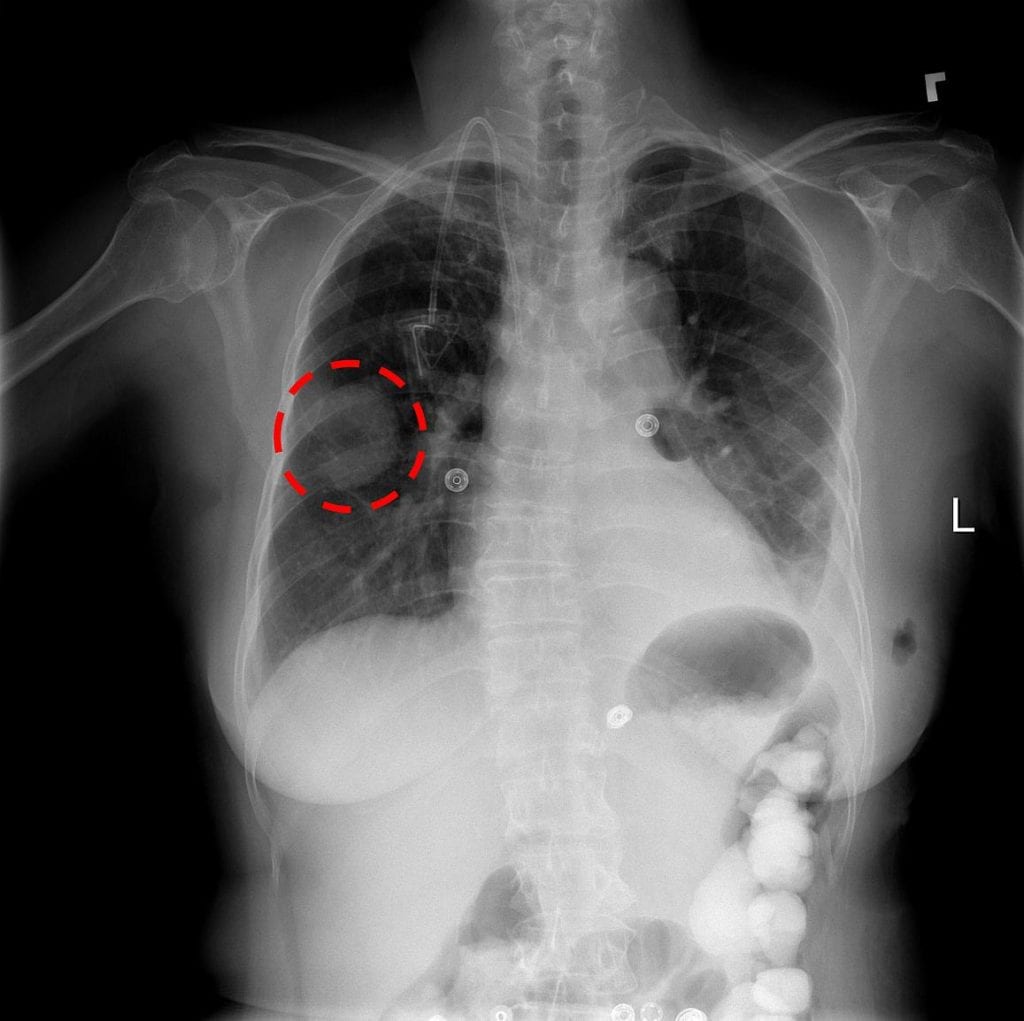

A chest x-ray identifies a lung mass.

Reading and diagnosing chest x-ray images may be a relatively simple task for radiologists but, in fact, it is a complex reasoning problem which often requires careful observation and knowledge of anatomical principles, physiology and pathology. Such factors increase the difficulty of developing a consistent and automated technique for reading chest X-ray images while simultaneously considering all common thoracic diseases.